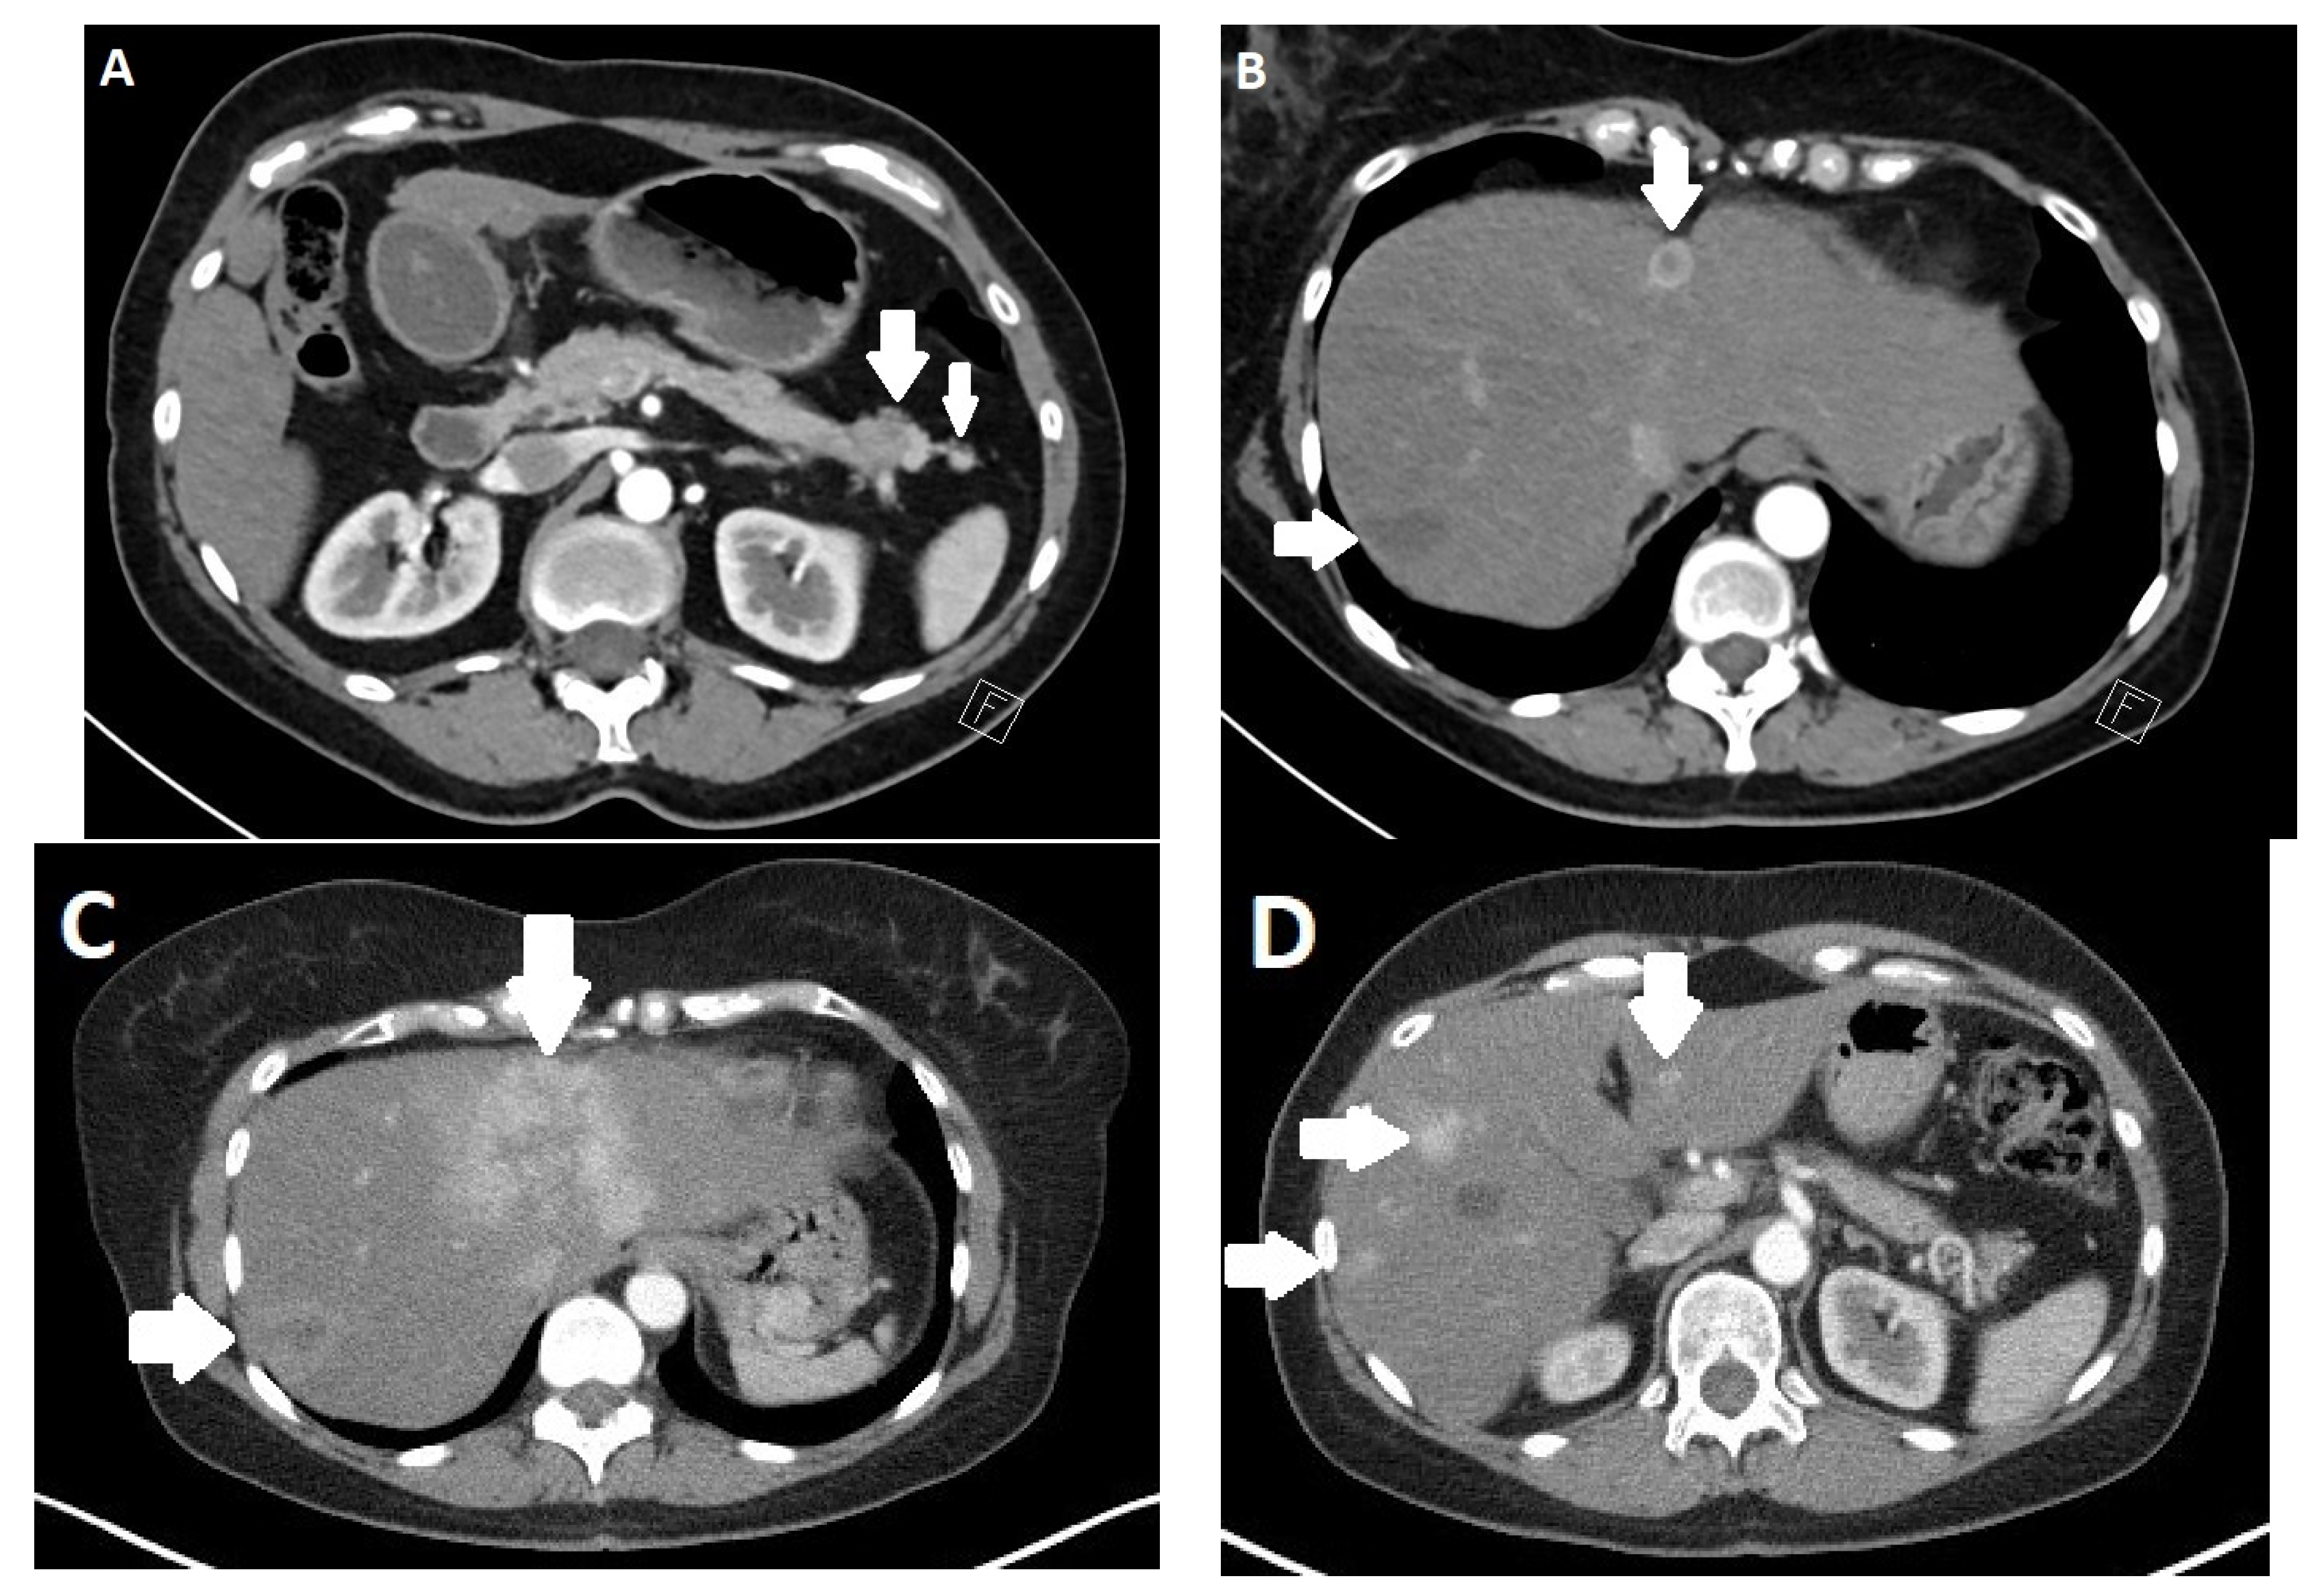

- Kim, J.H.; Eun, H.W.; Kim, Y.J.; Lee, J.M.; Han, J.K.; Choi, B.I. Pancreatic neuroendocrine tumour (PNET): Staging accuracy of MDCT and its diagnostic performance for the differentiation of PNET with uncommon CT findings from pancreatic adenocarcinoma. Eur. Radiol. 2016, 26, 1338–1347. [Google Scholar] [CrossRef] [PubMed]

- Prosperi, D.; Gentiloni Silveri, G.; Panzuto, F.; Faggiano, A.; Russo, V.M.; Caruso, D.; Polici, M.; Lauri, C.; Filice, A.; Laghi, A.; et al. Nuclear Medicine and Radiological Imaging of Pancreatic Neuroendocrine Neoplasms: A Multidisciplinary Update. J. Clin. Med. 2022, 11, 6836. [Google Scholar] [CrossRef]

- Gallotti, A.; Johnston, R.P.; Bonaffini, P.A.; Ingkakul, T.; Deshpande, V.; Fernandez-del Castillo, C.; Sahani, D.V. Incidental neuroendocrine tumors of the pancreas: MDCT findings and features of malignancy. AJR Am. J. Roentgenol. 2013, 200, 355–362. [Google Scholar] [CrossRef] [PubMed]

- Lee, L.; Ito, T.; Jensen, R.T. Imaging of pancreatic neuroendocrine tumors: Recent advances, current status, and controversies. Expert. Rev. Anticancer. Ther. 2018, 18, 837–860. [Google Scholar] [CrossRef]

- Owen, N.J.; Sohaib, S.A.; Peppercorn, P.D.; Monson, J.P.; Grossman, A.B.; Besser, G.M.; Reznek, R.H. MRI of pancreatic neuroendocrine tumours. Br. J. Radiol. 2001, 74, 968–973. [Google Scholar] [CrossRef]

- Bicci, E.; Cozzi, D.; Ferrari, R.; Grazzini, G.; Pradella, S.; Miele, V. Pancreatic neuroendocrine tumours: Spectrum of imaging findings. Gland. Surg. 2020, 9, 2215–2224. [Google Scholar] [CrossRef]